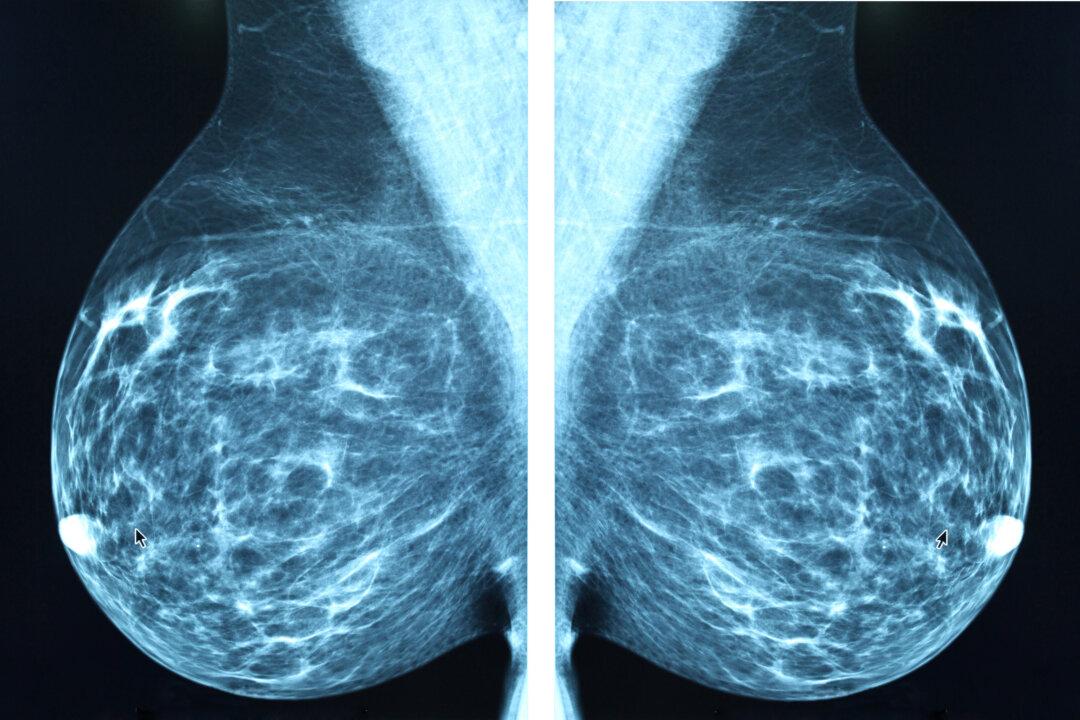

Advancements in artificial intelligence (AI) could provide breakthroughs in the way that we detect breast cancer and evaluate breast cancer risk.

A recent Swedish study found that AI was able to detect 20 percent more breast cancer than experienced radiologists—in addition to cutting their mammography reading workload by more than 40 percent. The study suggests that AI could be a useful tool for breast cancer detection as well as help doctors and radiologists to do their jobs more effectively.